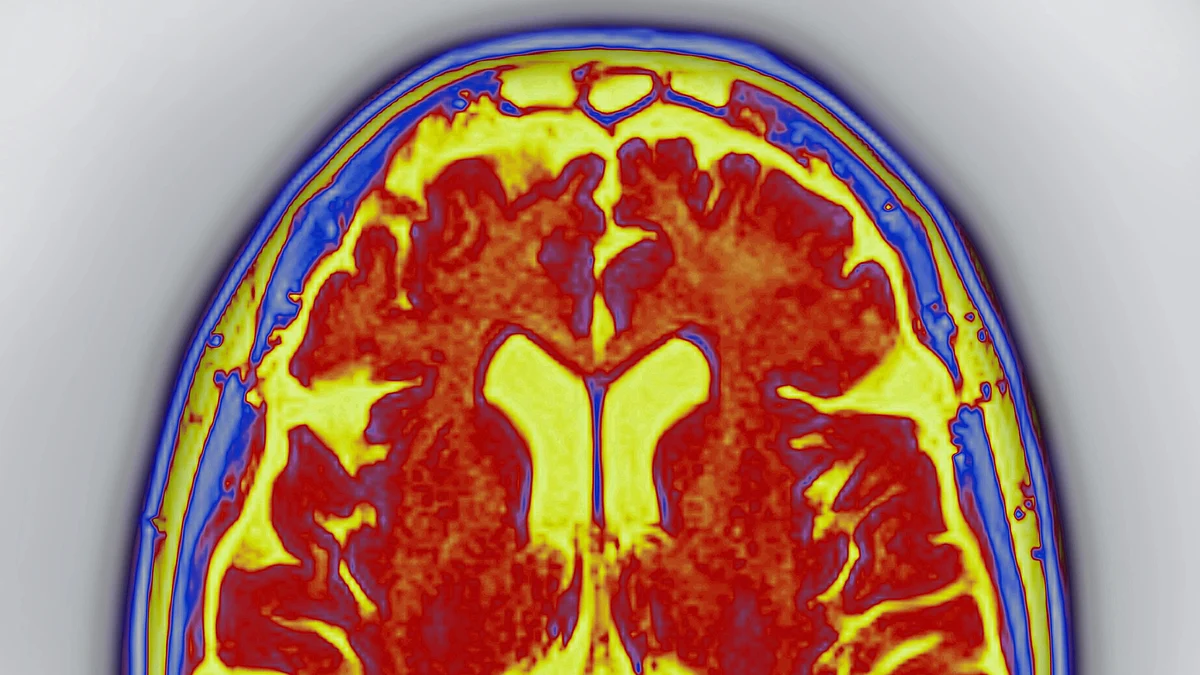

Dementia is more common in women than men. Atrial fibrillation is associated with a higher risk for cognitive impairment and dementia, possibly because the condition is linked with a more than two-fold risk of silent strokes.